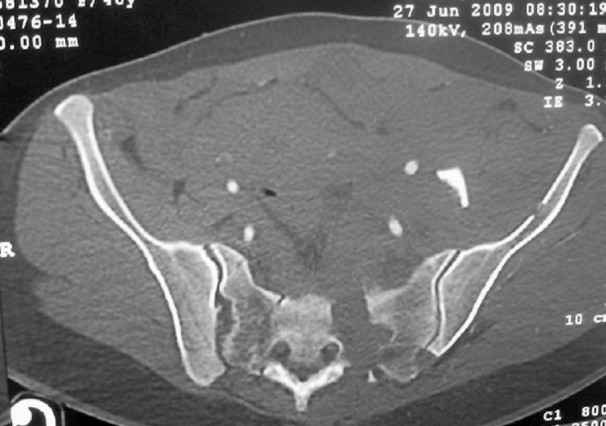

I'm posting this case on behalf of Dr. Pedro Caba, he is unable to post but able to read. 41 yo female , fall from 10 meters five days ago. Hemodynamically unstable on admission treated by angio and embolization and skeletal traction, with no external support. No associated injuries. Based on CT scan the pt has a both column fracture with conminuted dome and displaced anterior column and a sacral Denis 1 fracture with a displaced left ala. I think the best approach for the acetabular fracture is ilioinguinal with Smith-Petersen extension but don't know exactly the sequence . Will you start with the sacral fracture? Which technique? Thanks in advance Pedro Caba Unidad de Trauma Hospital 12 de Octubre Madrid Spain

The soft tissues are also in mild condition, buttock hematoma and probably a Morel-Lavalle. I send some more CT images. There are some conminution in the posterior column (I don’t have images now). The patient is scheduled for surgery next Monday. The plan is percutaneous sacral fixation and then ilioinguinal approach .

This complex and displaced sacral injury is likely an H pattern...2 hemipelvic components, an upper sacral component which remains attached to the lumbar spine, and a caudal sacral component...there are typically anterior ring injuries as well...in this patient's example, the left sided acetabulum also has been exploded.

Fixation stability can be reliably achieved for simpler and less displaced or less comminuted fractures using transiliac-transsacral screws...for most adults, these are usually 170-190mm lengths through the upper sacral segment after reduction.

For this patient (according to the limited imaging available), it would seem that a combination of lumbo-pelvic fixation along with transiliac transsacral fixation is optimal...BUT the left sided pelvic implants must be applied in consideration of and in anticipation of the necessary acetabular fixation implants.